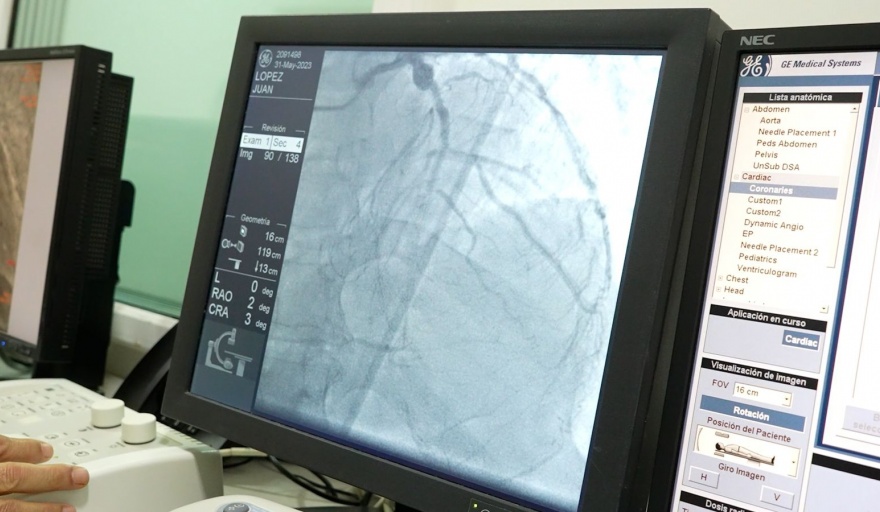

Pasó un poco más de un año desde que el Hospital Central de Pilar abriera sus puertas para comenzar a cuidar a los vecinos, un sueño hecho realidad para todo el distrito. Desde entonces, allí se atendieron miles y miles de pacientes. Pero hay un dato que se destaca especialmente: el Servicio de Hemodinamia del primer centro municipal de alta complejidad y emergencias superó los 1100 procedimientos realizados.

Este es un número muy importante de procedimientos, ya sea para acceder a un diagnóstico y a un tratamiento terapéutico de las áreas cardíacas, neurológicas y electrofisiológicas. La cifra representa que cada vez más pilarenses están accediendo a un sistema de salud de calidad y consolida al HCP como el hospital más importante de la región, especializado en alta complejidad y emergencias.

Es para destacar que es la primera vez en la historia del sistema sanitario público que se cuenta con este servicio, clave para la detección y tratamiento de este tipo de enfermedades. Los pacientes que fueron atendidos dentro de este servicio se encontraban padeciendo un infarto de miocardio, accidentes cerebrovasculares y arritmias graves, entre otras importantes complicaciones de salud.